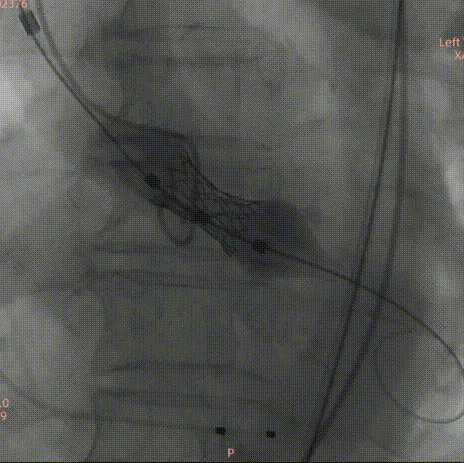

患者为70岁男性,主诉“咳嗽伴活动后气促一月”。超声显示主动脉瓣呈三叶,左冠瓣与右冠瓣融合呈一大瓣,与无冠瓣呈前后排列,瓣叶增厚,钙化明显,开放明显受限,关闭欠佳;主动脉瓣前向血流加快,平均跨瓣压差41mmHg;升主动脉增宽。

超声提示:主动脉瓣功能性二瓣化畸形,主动脉瓣重度狭窄并轻-中度关闭不全;三尖瓣少量反流;升主动脉增宽。

Type1 型二叶瓣,左右融合;收缩期瓣环:509.7mm²;收缩期流出道:516.0mm²;

法式窦空间大;STJ高度21.5mm,均径32.9mm;升主动脉增宽,40mm处均径42.0mm,最宽处约45.5mm;心脏角度53°;

LCA:16.3mm;RCA:14.4mm,法式窦空间大,考虑冠脉风险低;

瓣叶增厚,轻度钙化;

对合缘对齐(Commisure Alignment)角度为108°;室间隔膜部长2.2mm;

使用26mm瓣膜进行术前模拟;